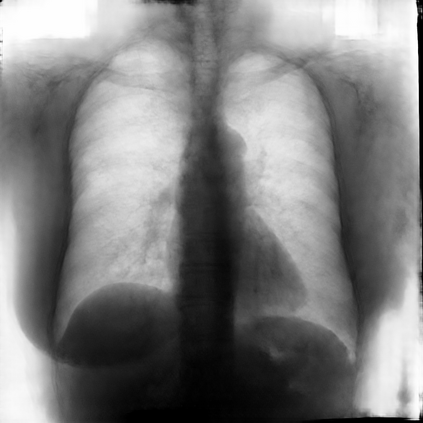

Multi-organ segmentation of X-ray images is of fundamental importance for computer aided diagnosis systems. However, the most advanced semantic segmentation methods rely on deep learning and require a huge amount of labeled images, which are rarely available due to both the high cost of human resources and the time required for labeling. In this paper, we present a novel multi-stage generation algorithm based on Generative Adversarial Networks (GANs) that can produce synthetic images along with their semantic labels and can be used for data augmentation. The main feature of the method is that, unlike other approaches, generation occurs in several stages, which simplifies the procedure and allows it to be used on very small datasets. The method has been evaluated on the segmentation of chest radiographic images, showing promising results. The multistage approach achieves state-of-the-art and, when very few images are used to train the GANs, outperforms the corresponding single-stage approach.